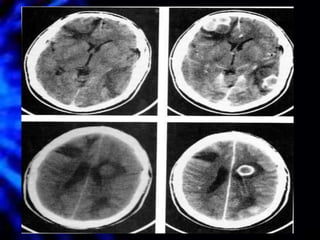

TC Cráneo

TAC Cráneo

• Sensibilidad del 95%

• Localización precisa del absceso

• Identificación de edema cerebral

• Diagnóstico de hidrocefalia secundaria

• Detecta desviación de línea media

• Con el uso de esteroides se altera la

morfología usual del absceso

– Pobre definición de la cápsula (sensibilidad se

reduce a 40%-60%)

TAC Cráneo • Sensibilidaddel 95% • Localización precisa del absceso • Identificación de edema cerebral • Diagnóstico de hidrocefalia secundaria • Detecta desviación de línea media • Con el uso de esteroides se altera la morfología usual del absceso – Pobre definición de la cápsula (sensibilidad se reduce a 40%-60%)